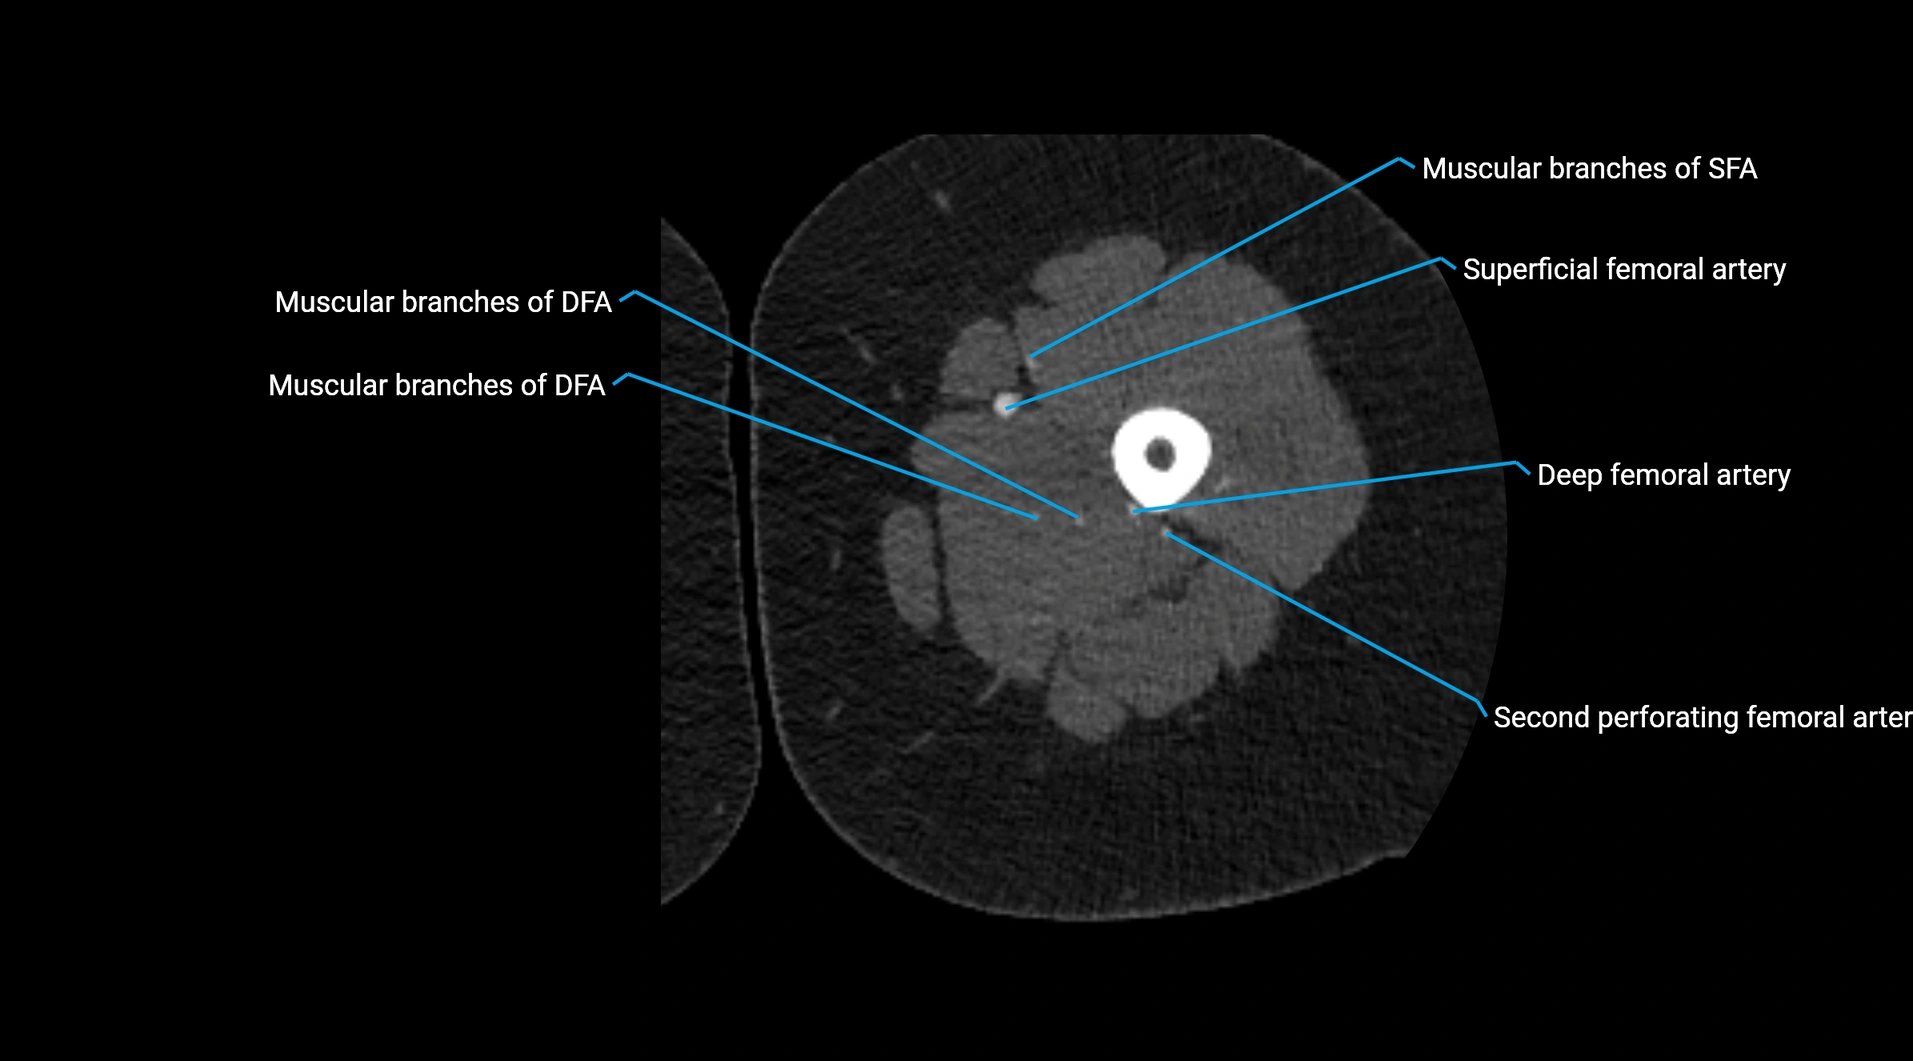

CT images

image

Contrast-enhanced CT (CTA):

• Gold standard for abdominal aortic imaging

• Provides excellent detail of lumen, wall, aneurysm, thrombus, and branch vessels

• Multiplanar and 3D reconstructions help in aneurysm measurement, stent graft planning, and dissection evaluation